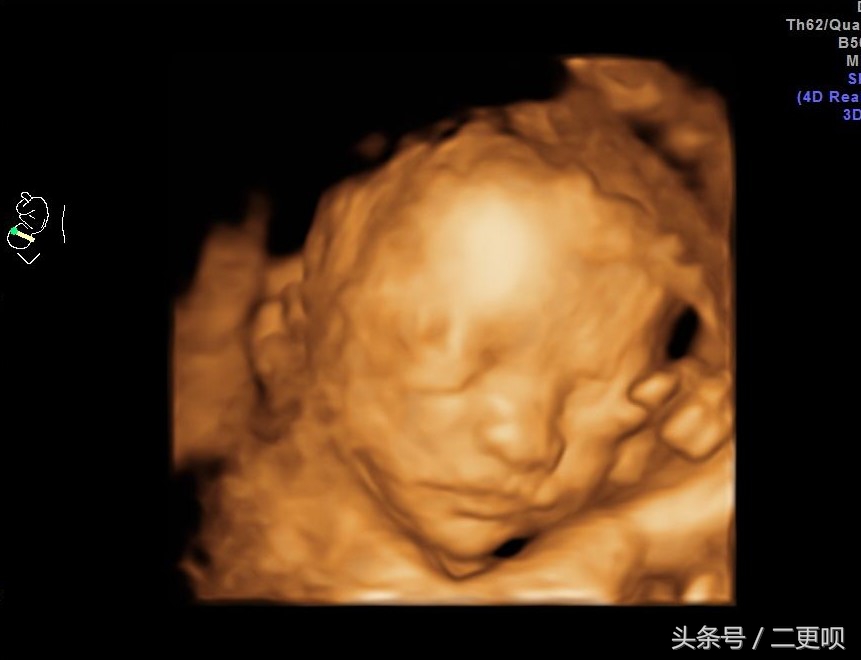

表妹24周肚子照

第一次表妹提前预约了四维彩超,很是开心,毕竟终于可以看到胎宝宝的脸了,本是很开心的事儿,可是很不幸,照到宝宝左侧侧脑室宽8MM,医生叫表妹半个月去复查,如果有增加,就要去市里人民医院检查。